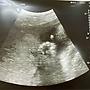

5Fgracenov16: https://i.imgur.com/ry4PUEi.jpg 我的寶寶去年情03/21 15:39

6Fgracenov16: 人節當天很會 連醫生都說手比愛心XD03/21 15:39